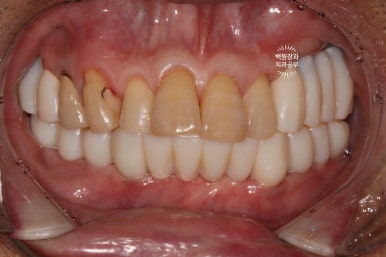

드디어 전체임플란트가 완성되었습니다!!

짜잔!!! 정말 비슷한 색상으로 제작이 잘 되어왔습니다.

최종 크라운을 연결하고나니 그렇게 깔끔할수가 없네요.

정면 사진입니다.

무면허업자에게 치료 받으셨던 어금니는 이제 하얀 지르코니아 크라운을 가진 임플란트로 대체되었습니다.

아래 틀니는 사라지고, 이젠 고정식의 임플란트로 바뀌었네요!

작은 충치들은 치아색의 레진으로 치료되어, 최종 치료결과는 아주 만족스러움 그 잡채!